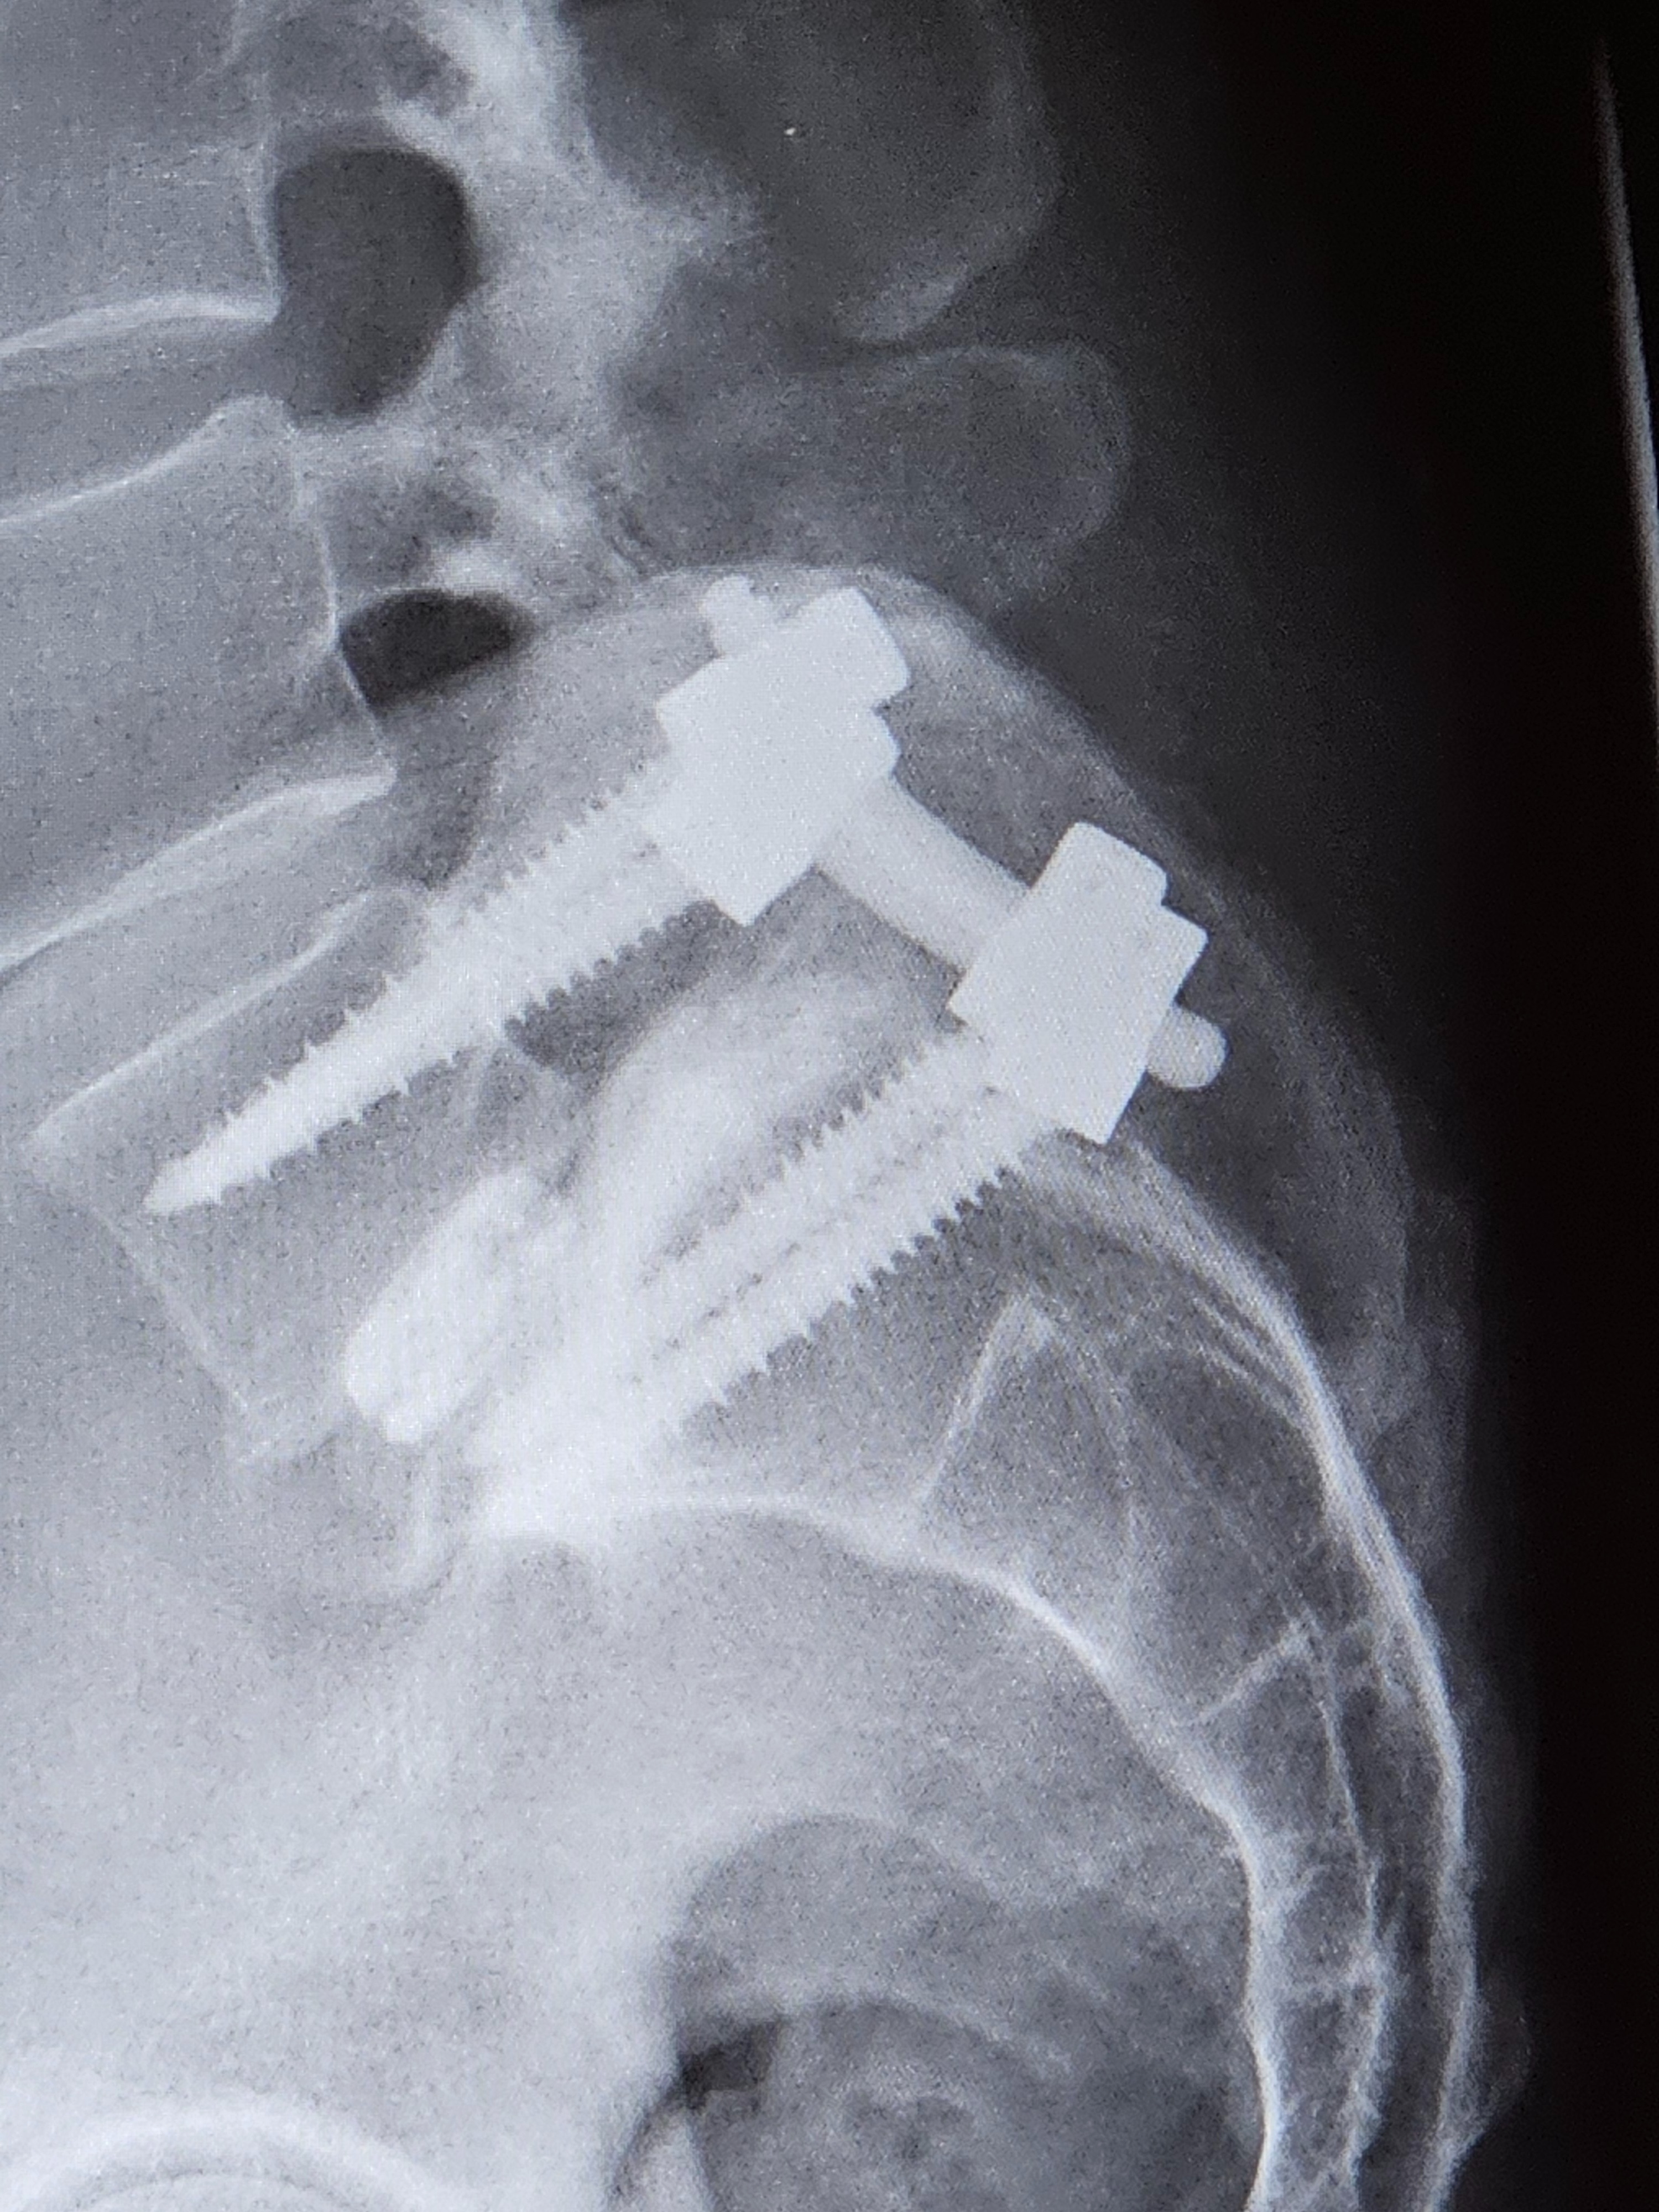

Hi, my name is Daniel Challburg and I am suffering from a incapacitating lower back injury from working in plumbing trades. I am a journeyman plumber with U.A. Local#343. I started feeling my disability in December of 2023. I reported my injury to my supervisor with an x-ray from my health provider, which is when my supervisor then instructed me to take some time off work before the Christmas holiday to try and get better. It is now October 19th, 2025 and I have not been able to return to work. I currently am trying to get Social Security Disability in California but they keep telling me that they are backed up. I have pulled a lump sum from my retirement to live off of but that money is vanishing fast every month. I need financial help! My wife works full time as a DUI Councelor but her money will not cover everything, since I've been disabled. I used to be the bread-winner and now all I can do is pray that I get better. I do physical therapy almost everyday and it usually only works when I'm using my pain medication. I went through a spinal cord stimulation trial on October 8th thru October 15th. The surgeon took the stimulation device out and now I'm experiencing severe pain levels again. I am getting a permanent spinal cord stimulation surgery in the future but am waiting for the surgeon to set the date up. Will you please help my family out financially during my difficult time. I have never asked for this type of help before and if and when I get better I would like to pay it forward for someone who needs help like I do. God bless